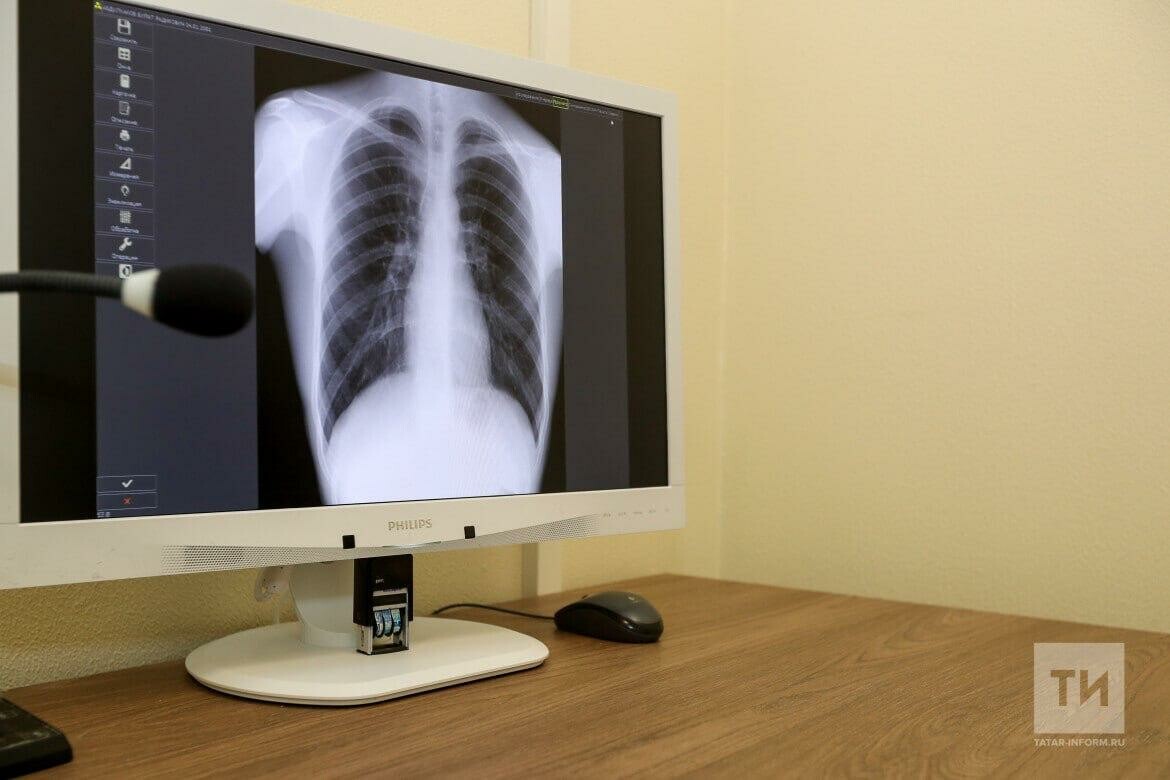

Врачи рассказали, как спастись от пневмонии

Идет неделя профилактики заболеваний органов дыхания, которая завершится 12 ноября Всемирным днем борьбы с пневмонией. «Татар-информу» в Республиканском центре общественного здоровья и медицинской профилактики рассказали о том, как защититься от этой болезни.

Пневмония – это острое заболевание, вызывающее воспаление легких. Воспаление происходит из-за микроорганизмов – патогенов. Чаще всего возбудителями внебольничной пневмонии являются пневмококки. Однако болезнь может возникнуть при инфицировании другими бактериями, вирусами или простейшими. Кроме того, у пациентов с пневмонией бактерии и вирусы могут быть обнаружены одновременно.